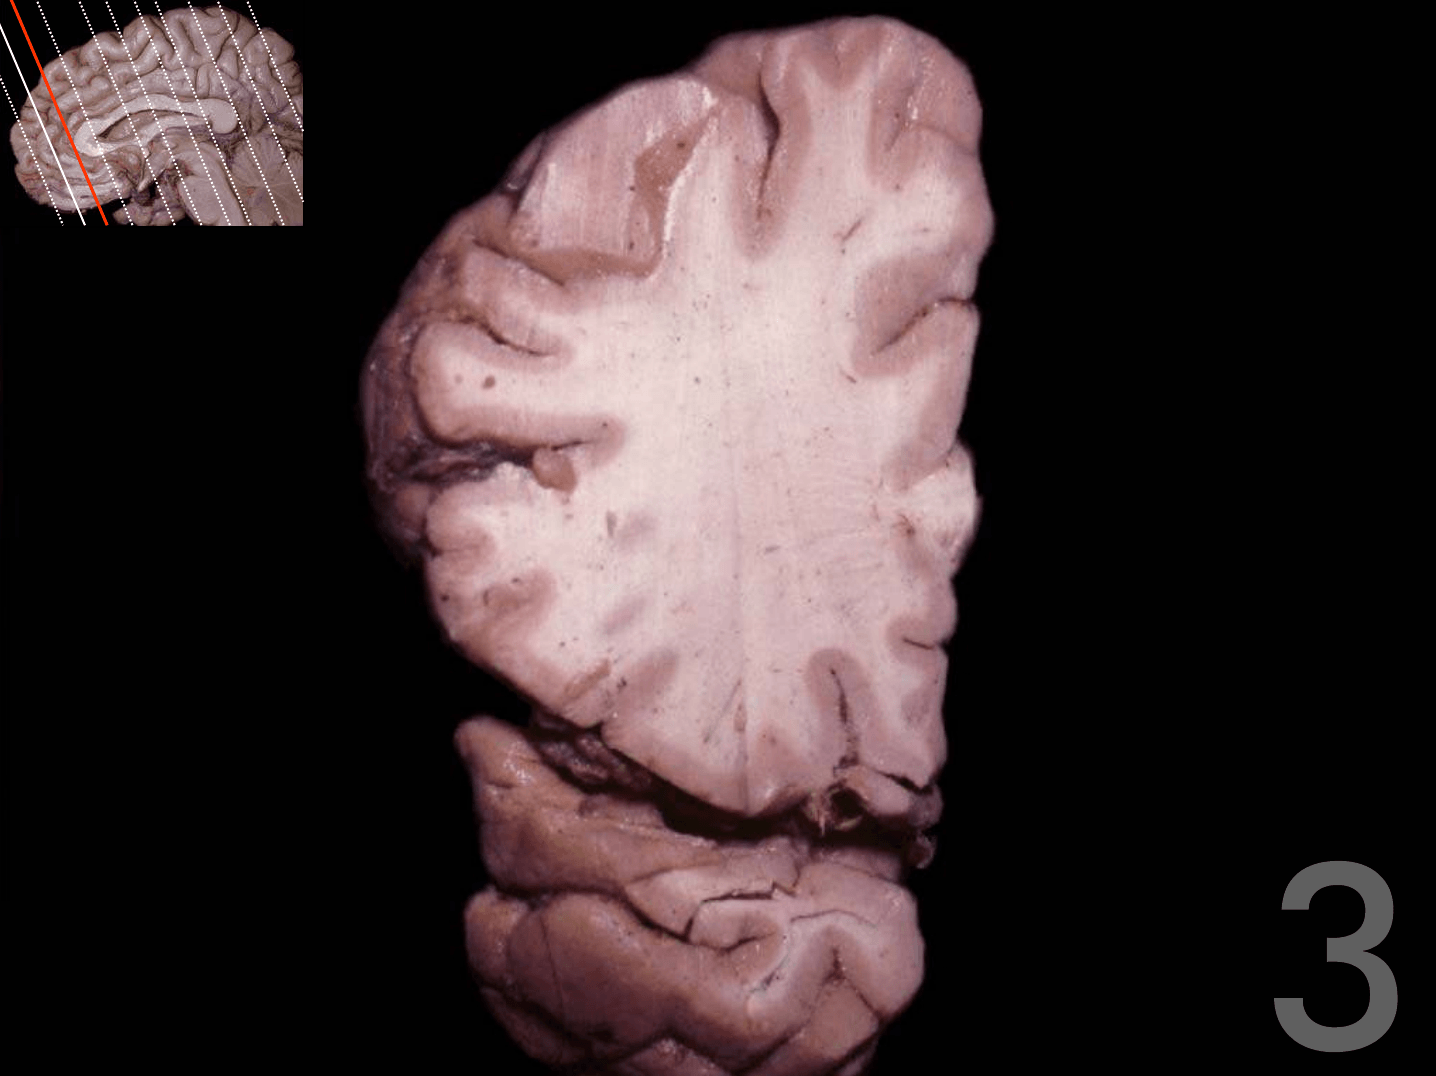

Tronco del cuerpo calloso

Rodilla del cuerpo calloso

Columna del fórnix

Comisura anterior

Foramen interventricular

Infundíbulo

Habénula

Pico del cuerpo calloso

Acueducto del mesencéfalo

Estría medular del tálamo

Adhesión intertalámica

Lámina terminal

Quiasma óptico

Tubérculo mamilar

Comisura posterior

Glándula pineal

Rodete del cuerpo calloso

Calota mesencefálica

Túber cinereum